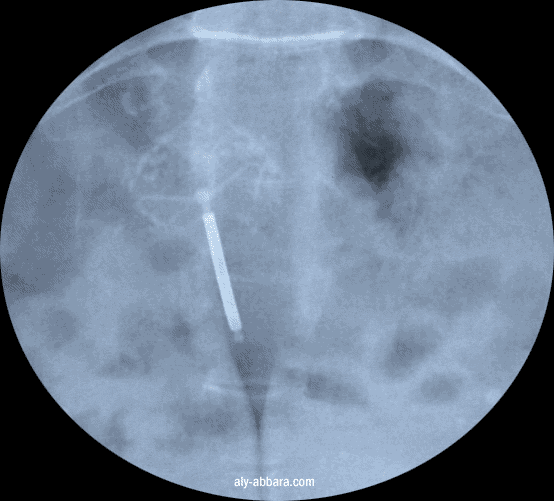

Fibrome utérin (myome) sous séreux calcifié et un stérilet au cuivre

Radiographie

du pelvis sans préparation montrant la présence :

d'un

stérilet au cuivre

(dans la cavité utérine à l'échographie)

en arrière plan ou trouve une nuage de calcifications dues à la présence d'un

myome utérin

sous séreux, calcifié de la paroi postérieur du corps utérin

(voir ce fibrome à l'IRM)